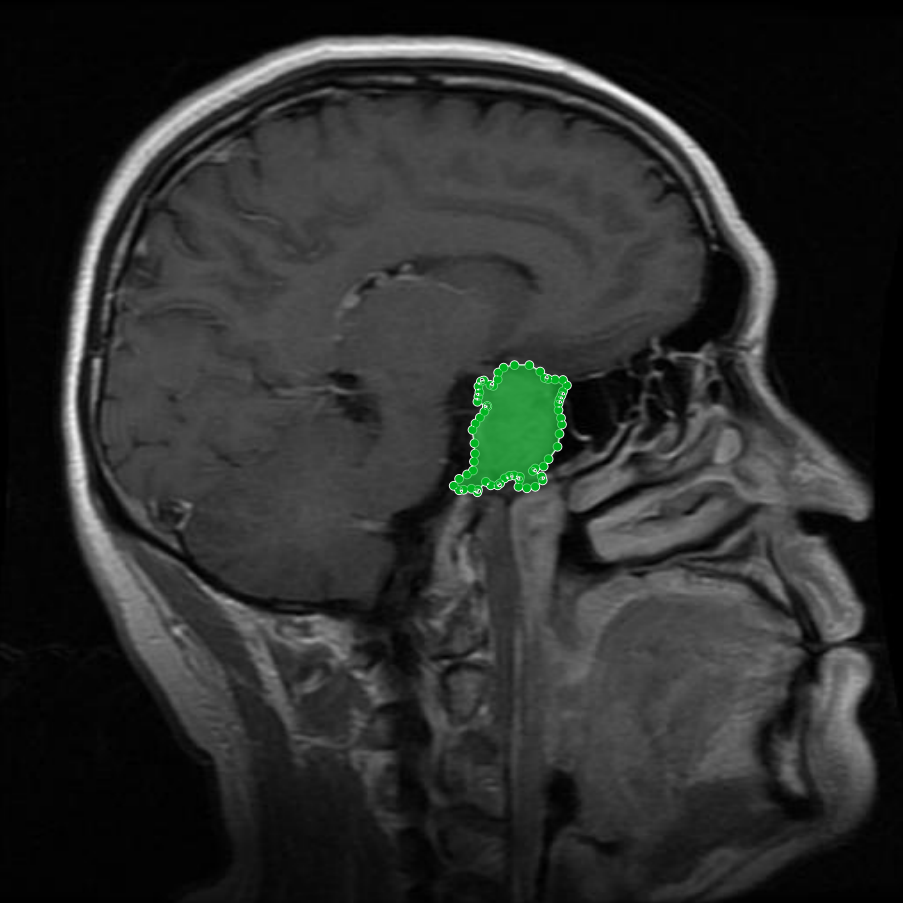

Meningioma: Meningiomas arise from the meninges and are generally well‑circumscribed and homogeneous, making them easier to segment. However, their location adjacent to critical structures such as dural sinuses and cranial nerves can complicate diagnostic tasks. An example of a meningioma and its segmentation mask is presented in Figure 2, illustrating the clarity of its boundaries.

Figure 2: Samples of Meningioma segmentation across different imaging planes